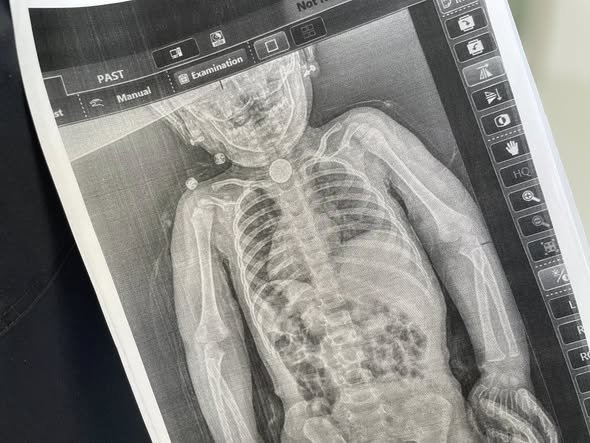

У перші дні весни у дитини з’явилися нові небезпечні симптоми: блювання, відмова від їжі, покашлювання та свистяче дихання, яке було чути навіть на відстані. Батьки знову повезли дочку до лікарні та наполягли на додатковому обстеженні. Дівчинці зробили рентген, який чітко показав стороннє тіло у стравоході.

Вже під час ендоскопічного обстеження точно встановили, що ж це було. У ділянці першого фізіологічного звуження стравоходу міцно застрягла кругла літієва батарейка діаметром 2,5 см. Навколо неї сформувалися набряк та гіпергрануляції слизової оболонки — ознаки тривалого ушкодження тканин.